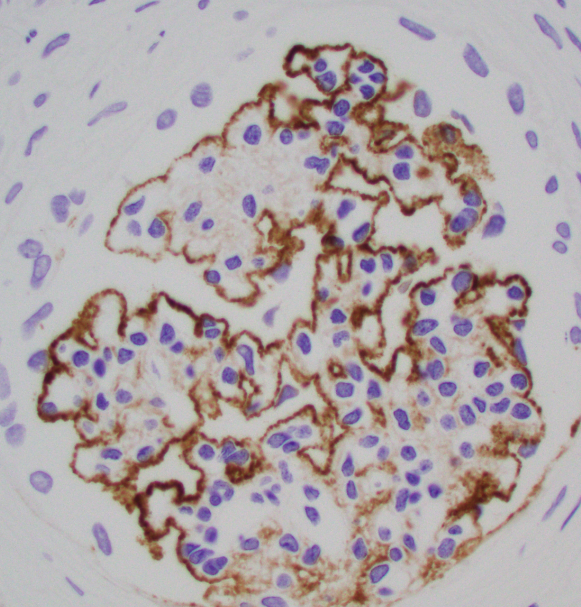

Teenager with nephrotic syndrome. Biopsy revealed unusual case of membranous nephropathy in a peds patient. PLA2R positive (IHC). PLA2R most common antigen in peds MN. EXT2 also common, SEMA3B less common. ( https://t.co/zEASwdQXIe)

#renalpath #pathsky #nephsky